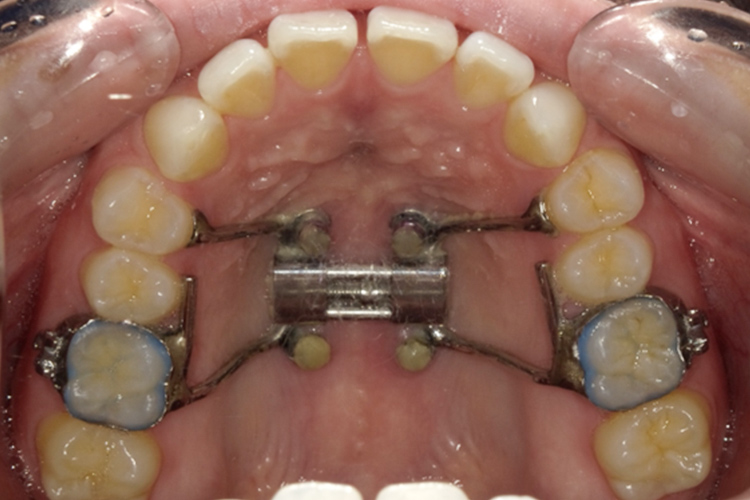

小児上顎拡大装置

| 費用 | 77,000円 |

|---|---|

| 治療期間 | 約3ヶ月~6ヶ月 |

| メリット |

上顎の成長を促すことで歯列や骨格のバランスを調整して不均衡を改善できる。 永久歯に生え変わる前に治療することで、永久歯が生えてきた際のスペースを確保できるため、便宜抜歯するリスクを回避できる。 上顎が広がり、鼻腔が広がることで、口呼吸から鼻呼吸へ改善できる。 |

| デメリット |

装置装着後一週間ほどは発音しづらかったり、飲み込みにくく感じる。 口元や鼻に痛みが生じる場合があり、装置周辺に食べ物が付着しやすいため、歯磨きの難易度が高くなる。 |

矯正前

拡大装置

拡大後

ブラケット

矯正後